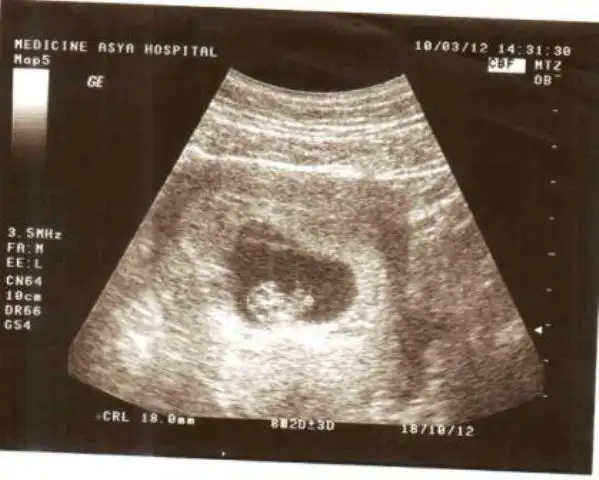

beimde bebişim bu :nazar: :nazar: :nazar: :nazar: :49: hamd olsun bu günleri gördük

Eki Görüntüle 367241

lann sevo senin bebek kocaman olmuş haa maşallahh :nazar::nazar::nazar::nazar::nazar::nazar::nazar::nazar::nazar:

diymi teyzesi büyümüşşş :1: :nazar: :nazar: hala inanamıyorum biliyomusun :31:

bu arada senin bebişin sol tarafta duruyor bebişinin konumuna göre ERKEK olacak bebeğin :emir_bebek::nazar: